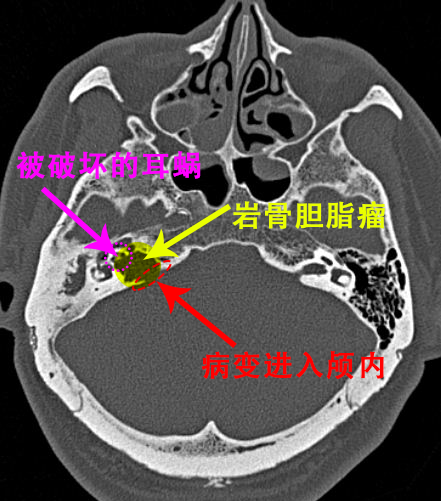

顼晋昆追问病史发现,患者除了面瘫,还伴有耳聋和眩晕等症状,建议患者完善耳部颞骨CT,结果提示居然是颞骨岩部胆脂瘤,这才是导致其面瘫的罪魁祸首。更可怕的是,胆脂瘤不仅破坏了颞骨,也已经进入颅内,紧贴脑干部位!

岩骨属于颞骨的一部分,人体有两块岩骨,像螺丝钉一样镶嵌在耳朵部位的深处,与上方的大脑关系紧密。

很多人可能对“岩骨胆脂瘤”这一词比较陌生,甚至不知道岩骨在人体的哪个部位。但岩骨胆脂瘤是一种并不少见、且较为危重的耳科疾病。

岩骨胆脂瘤又称表皮样瘤,并非真性肿瘤,本质上属于良性病变,但它具有极强的侵蚀破坏能力

颞骨内有支配面部肌肉活动的面神经以及掌管听力的听神经和躯体平衡的前庭神经,如果胆脂瘤侵蚀了以上神经,就会出现面瘫、听力下降、眩晕等症状。

若胆脂瘤侵蚀掉颞骨的骨质,继续向上侵蚀保护大脑的颅骨,则会导致脑膜炎、脑脓肿等严重后果。